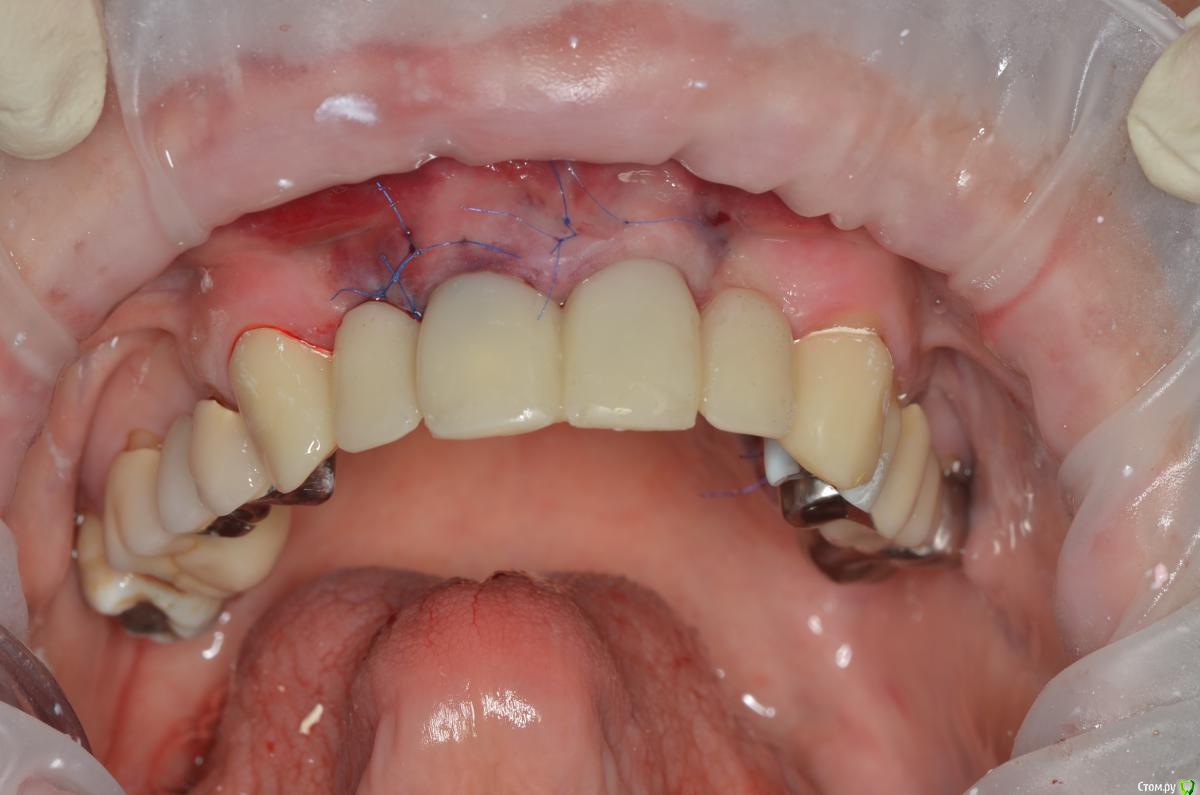

gangsta85 Опубликовано 27 сентября, 2016 Поделиться Опубликовано 27 сентября, 2016 Здравствуйте, уважаемые коллеги.Помогите пожалуйста разобраться.Центральные резцы в\ч были удалены и установлено 2 имплантата с пластикой десны, 12,22 отсутствуют в области 12 трансплантация слизистого лоскута.В тот же день изготовлены времянки по ключу с ваксапа. профиль трансгингивальной части сделан максимально под размер постоянной реставрации. 12,22 овоиды плотно прилегающие к десне.Вопросы:- Можно ли изготовить времянки сразу по форме максимально похожей на будущие реставраций и свести к минимуму коррекции профиля десны?- можно ли сделать надрез в области 22 и максимально погрузить в десну овоид 22, насколько плотно можно прижать овоид 11 в области слизистого трансплантата?- можно ли в такой ситуации добиться формирования десневых сосочков в области 12,22?-через какое время можно снять времянки для коррекции?- постоянная реставрация через 4 месяца? Что если снять слепок в день операции в лаборатории отфрезеровать времянки и установить через 1-2 дня , удастся ли в программе отмоделировать правильный профиль десны и овоиды? Как бы вы предпочли сделать времянки на CAD\CAM или в ручную? Ссылка на комментарий

gangsta85 Опубликовано 28 сентября, 2016 Автор Поделиться Опубликовано 28 сентября, 2016 Вы хотите на временных коронках на имплантах в области 11 и 21 сделать еще консольные единицы на латеральные резцы?Планируется постоянная конструкция с опорами на 11,21 и консолями 22, 12 на сколько я знаю специалисты так делают и имплантаты не будут перегружены.Немедленную нагрузку предложил хирург для эстетики и объема десны и я с ним согласен. Ссылка на комментарий